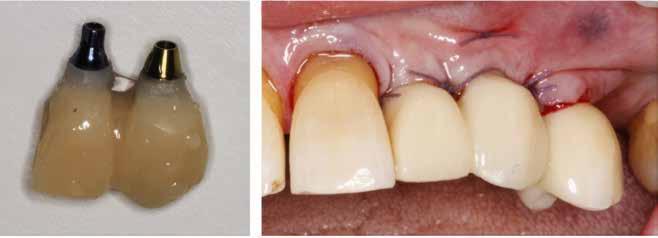

Klik ind på Tandlægebladet.dk og opret en reklamation, så sørger vi for, at bladet lander i din postkasse.

Klik ind på Tandlægebladet.dk og vælg om os

BAGGRUND – Transverselle okklusionsafvigelser kombineret med en vækstbetinget kæbedeformitet korrigeres sædvanligvis ved en sektioneret Le Fort 1-osteotomi eller kirurgisk assisteret ganeekspansion. Ved ekstreme transverselle skeletale diskrepanser mellem maksillen og mandiblen kan der være indikation for transversel udvidelse af mandiblen ved hjælp af mandibulær midtlinjeosteotomi eller mandibulær midtlinjedistraktionsosteogenese.

PATIENTTILFÆLDE – En 15-årig dreng med infantil autisme blev henvist fra Hjørring Kommunes Tandpleje til Kæbekirurgisk Afdeling, Aalborg Universitetshospital, for ortodontisk-kirurgisk behandling af et stort horisontalt maksillært overbid uden kontakt på nogen af tænderne. Den vækstbetingede kæbedeformitet blev korrigeret ved hjælp af ortodonti og mandibulær midtlinjedistraktionsosteogenese efterfulgt af en sektioneret Le Fort I-osteotomi og bilateral sagittal splitosteotomi.

KONKLUSION – Mandibulær midtlinjedistraktionsosteogenese er en forudsigelig behandlingsmodalitet til transversel udvidelse af mandiblen. Imidlertid er behandlingen forbundet med en betydelig risiko for recidiv samt biologiske og tekniske komplikationer, hvorfor mandibulær midtlinjedistraktionsosteogenese udelukkende anbefales til korrektion af ekstreme vækstbetingede transverselle okklusionsafvigelser.

EMNEORD Jaw abnormalities | malocclusion | orthodontics | orthognathic surgery

PERNILLE SAGBAKKEN, tandlæge, Odontologisk Institut, Det Sundhedsvidenskabelige Fakultet, Københavns Universitet

ANNETTE DALGAARD KJELLERUP, specialtandlæge i ortodonti, Kæbekirurgisk Afdeling, Aalborg Universitetshospital

THOMAS STARCH-JENSEN, klinisk professor, overtandlæge, specialtandlæge i tand-, mund- og kæbekirurgi, postgraduat klinisk lektor, ph.d., Kæbekirurgisk Afdeling, Aalborg Universitetshospital, og Klinisk Institut, Det Sundhedsvidenskabelige Fakultet, Aalborg Universitet

Accepteret til publikation den 12. december 2024.